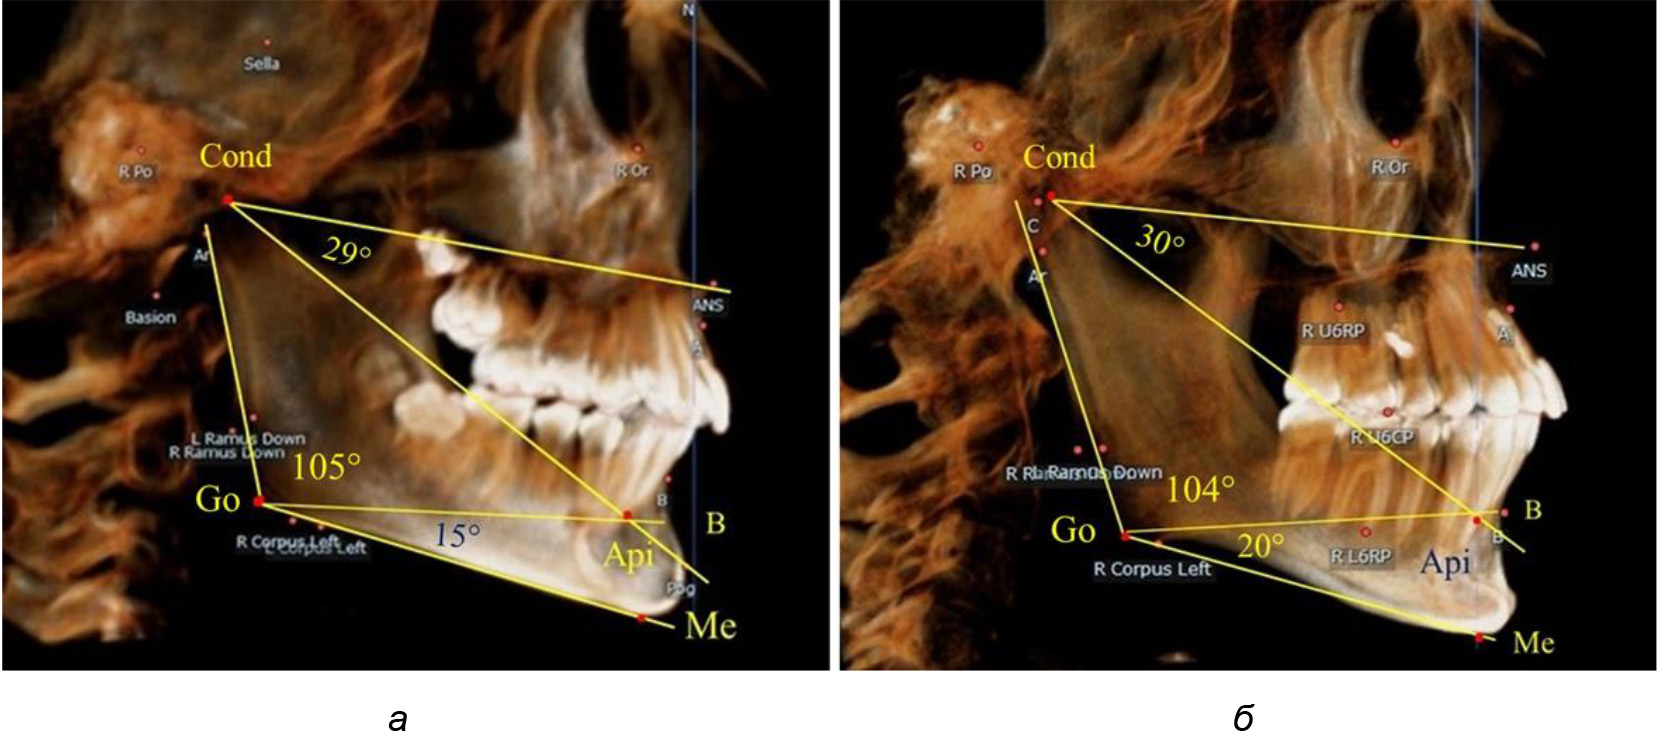

После смены всех молочных зубов (анализ 9 ТРГ) и после прорезывания вторых постоянных моляров (7 человек) происходил очередной этап подъема высоты прикуса с увеличением размеров костей гнатической части лица. Однако величина основного угла гнатической части лица SNA-Cond-Api, так же как в молочном и сменном прикусе, в норме составляла (30,02 ± 1,25)°, что не имело достоверных различий (р ˃ 0,05) с аналогичным параметром, анализируемом в других группах исследования. Угол нижней челюсти и его составляющие отличались вариабельностью параметров при различных показателях нижнечелюстного угла (рис. 6).

Рис. 6. Варианты 3D рентгенограмм детей после смены всех молочных зубов (а) и после прорезывания вторых моляров (б)

Таким образом, данные, полученные при исследовании детей с физиологическим прикусом в различные периоды онтогенеза, показали, что величина основного угла гнатической части лица SNA-Cond-Api была относительно стабильным параметром, вне зависимости от линейных параметров челюстных костей. Данный показатель может служить ориентиром для дифференциальной диагностики зубоальвеолярных и гнатических форм аномалий окклюзии в вертикальном направлении.